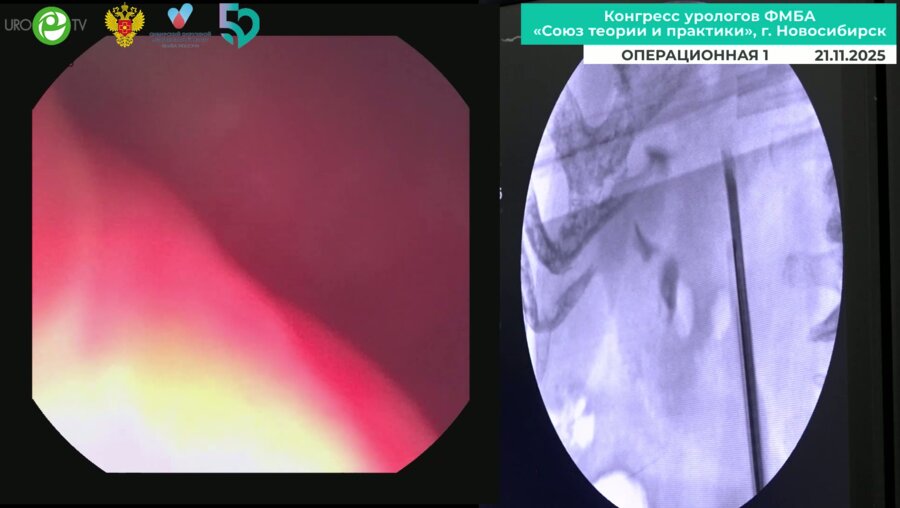

Мочекаменная болезнь